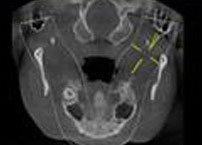

术后CT 手术完全成功 术后CT 手术完全成功